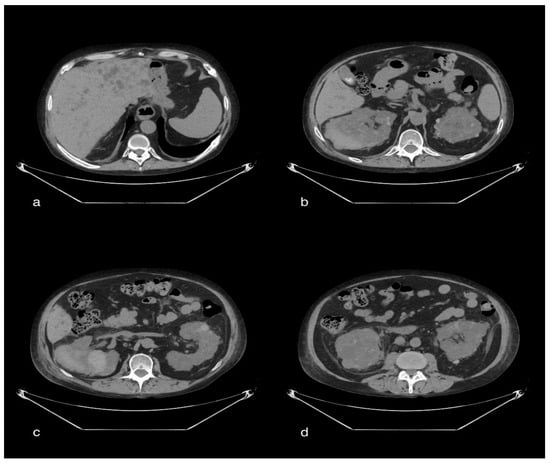

3.4.2. CT Imaging Finding

The chest CT showed, bilaterally, the presence of multiple densitometric areoles of the GGO type with predominant subpleural distribution, especially in the slopes, with thickening of the interlobular septa with a “crazy paving” pattern. Three was also widespread ventilation phenomena. Pericentimetric lymphadenomegalies were observed in mediastinum. Visual Score: LSD: 25–50%; LM: 0–25%; LID: 25–50%; LSS: 25–50%; LIS: 25–50%. Abdomen CT revealed, on the anteromedial side of the right thigh, the marked and wide-spread imbibition of the soft tissues due to evidence of contrast medium (arterial) extravasation in correspondence with the anterior side by two collateral branches of the superficial femoral artery, homolateral to the middle III and the III distal as a sign of active bleeding in the lower limb (Figure 4).

Figure 4. A 85-year-old female patient in whom we observe, in the late phases of the study, a marked and diffuse imbibition of the soft tissues on the antero-medial side of the right thigh due to evidence of extravasation of mdc (arterial) in correspondence of the anterior side by two collateral branches of the superficial femoral artery ipsilateral to the middle III and distal III, as well as signs of active bleeding.

CT showed, bilaterally, the presence of multiple densitometric areoles of the GGO type with predominantly subpleural distribution with thickening of the interlobular septa with a “crazy paving” pattern. Lymphadenomegalies were observed in the mediastinum as well as ventilating phenomena. The volumetric increase in the right abdominal muscle of about 104 × 73 mm in the axial plane with a craniocaudal extension of about 28 cm, with inhomogeneous hypo/hyperdense densitometry, referred to as a hematoma, was reported. The pelvic excavation appeared to be occupied by a voluminous fluid/superfluid collection (dAP 20 cm × dcc 10 cm) spontaneously hyperdense in its most descending hematic part, appreciable in the context of two ecstatic vascular structures that were evident only in the portal and late phases of the study, compatible in the first hypothesis of venous bleeding. The uterus and the catheterized bladder appear to laterodeviate to the right. Further super-fluid collection with similar densitometric characteristics can be appreciated in the peri- and sub-renal site, posteriorly to the left with signs of hematic infarction of the ipsilateral psoas, which appears to have increased in volume. There was also a thin layer of pouring in the perihepatic area (Figure 3).

Figure 3. A 75-year-old female patient with volumetric increase in the rectus muscle of the right abdomen of approximately hypo/hyperdense inhomogeneous densitometry due to hematoma. The pelvic cavity appears to be occupied by a voluminous fluid/overfluid collection spontaneously hyperdense in its more declivity.